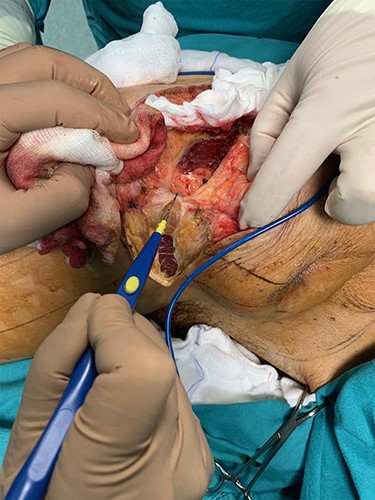

During the operation, surgeons exposed meticulously the liposarcoma that was utterly removed, and performed elective resection of the right iliac crest, the upper part of the sartorius muscle, part of the gluteus maximus muscle, and part of the muscles of the anterior abdominal wall in order to eliminate the potentiality of local recurrence of the liposarcoma (Figs. 5–7). The operation was uneventful, and two drainages were placed into the pelvic fossa. The drainages were removed the sixth postoperative day when the patient was finally discharged with instructions. The pathology report documented a well-differentiated liposarcoma of the right pelvic fossa. Finally, at the 6-month follow-up, the patient had no complication or recurrent lesions and oncologists declared that adjuvant therapy was not essential.

Elective resection of the right iliac crest and part of the right gluteus maximus muscle.